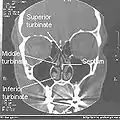

حفرهٔ بینی (کاواک بینی، خَیشوم) محفظهای بزرگ و پر از هوا است که در عقب و بالای بینی در میانههای صورت قرار گرفته است. حفره بینی از منخرها (سوراخهای بیرونی بینی) تا کوآنها (سوراخهای عقبی بینی) ادامه دارد و مفروش با مخاط است.[1] حفره بینی توسط سوراخ های خلف بینی به حلق مربوط می شود.

ابعاد تقریبی حفره بینی انسان شامل بلندی ۵ سانتیمتر، درازای ۵ تا ۷٫۵ سانتیمتر و پهنا از نزدیکی کف ۱٫۲۵ سانتیمتر است. پهنای سقف بینی در یک حفره حدود ۲ میلیمتر است.